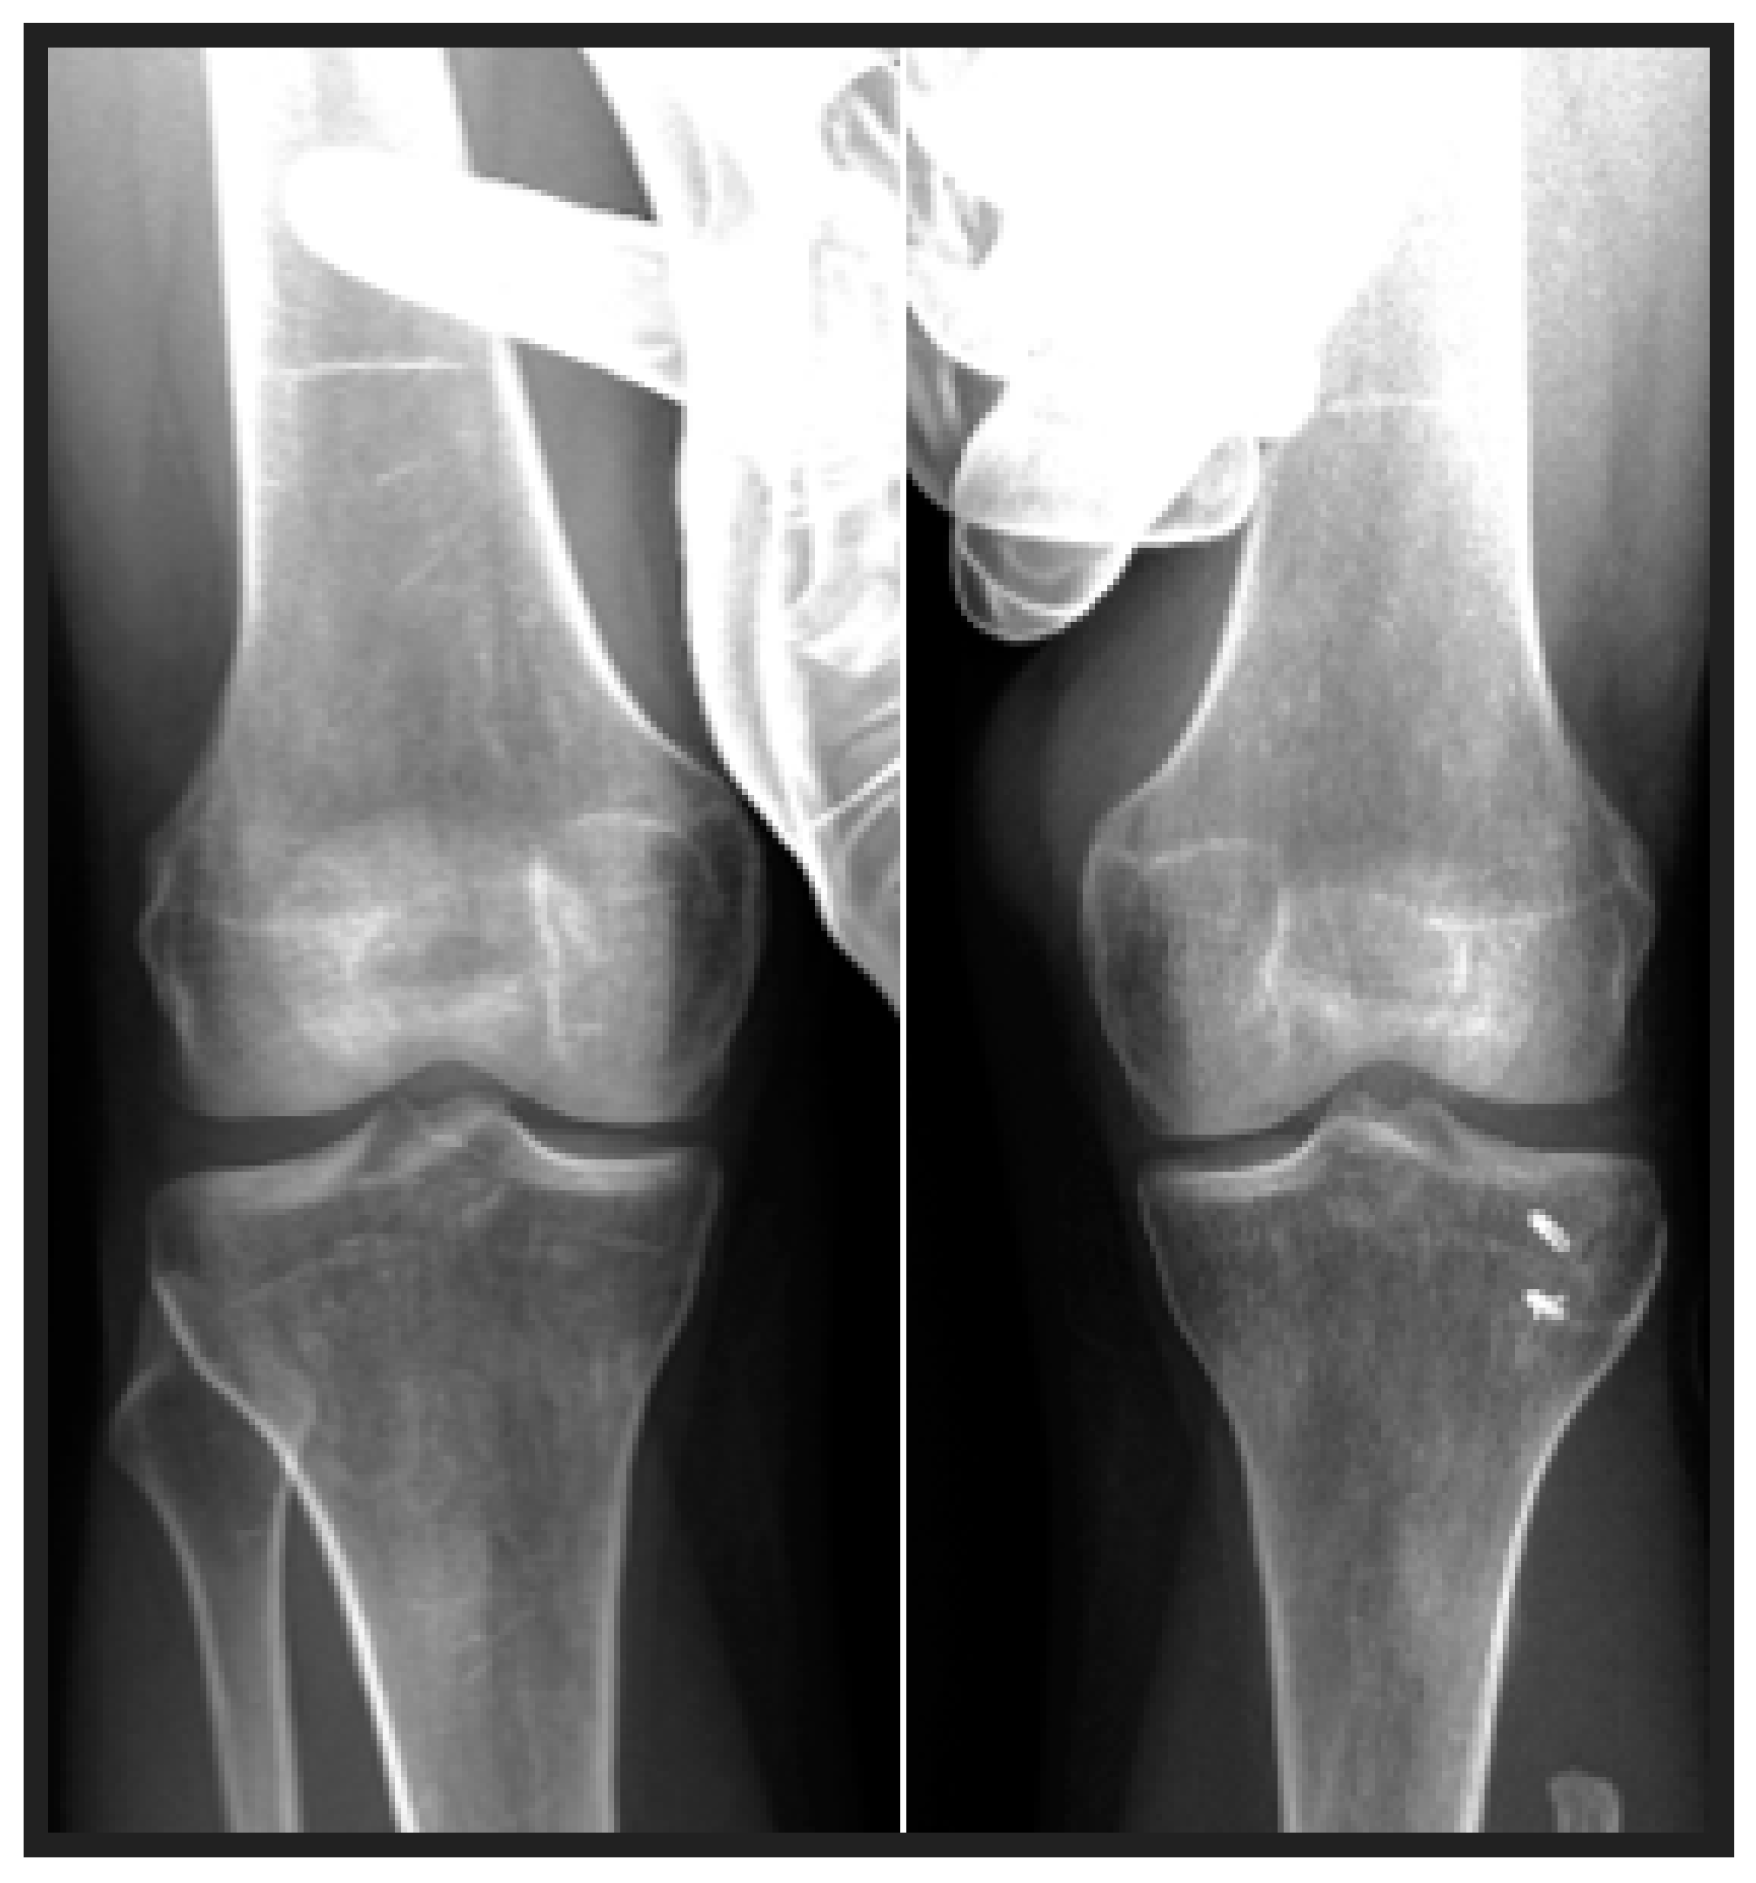

Proximal Fibula Resection for Tumors—Case Series and Technical Note

2. Methods